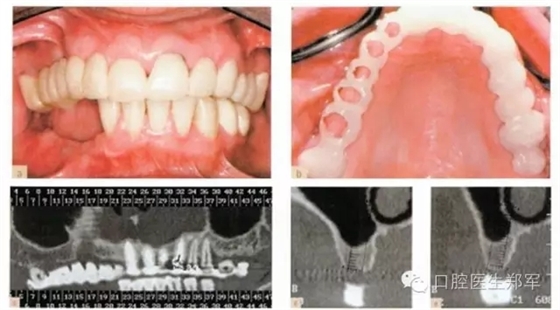

圖5 a-g 局部缺牙、美學(xué)缺陷、牙列缺損、后牙牙合支撐喪失、部分牙段過度萌出、咬合垂直距離中度喪失(圖片由Dr. 0 Ghelfan提供) |

•復(fù)制診斷蠟型制作暫時修復(fù)體和放射導(dǎo)板(圖8);

圖6 a-b 診斷蠟型 c 根據(jù)美學(xué)、生物力學(xué)和臨床冠高度的標準,設(shè)計咬合垂直距離。 |

圖8 a暫時過渡性修復(fù)體 b復(fù)制暫時義齒制作放射導(dǎo)板(丙烯酸和硫酸鋇) c-e 放射導(dǎo)板下,阻射的牙齒的CT放射影像。 |

圖9上頜竇提升術(shù)中,放射導(dǎo)板作為外科導(dǎo)板以指導(dǎo)種植體的位置和方向。 |